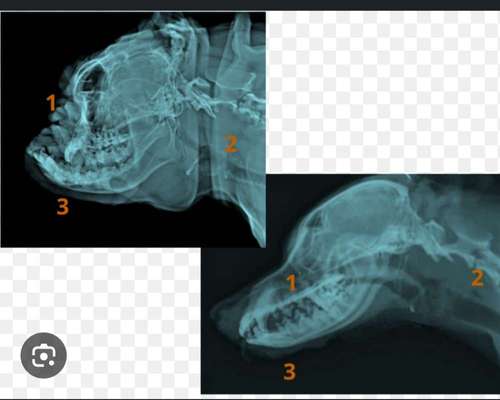

Ich finde das sagt alles! Normaler Hundekopf im Vergleich zu den Brachyzephalen Rassen. Das ist die Schädelform und das ist bei JEDER dieser Rassen gleich! Da gibt es keine mildere oder schwerere Form, das ist doch Quatsch!